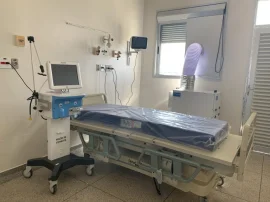

Ministério da Saúde envia 30 respiradores para Bauru; investimento ultrapassa R$ 1 milhão

Estado libera R$ 21 milhões para a abertura de leitos na região de Bauru

Ministério da Saúde corta o financiamento de leitos na região de Bauru

Bauru fica com 50 dos 227 novos leitos anunciados para a região

Deputado Rodrigo Agostinho anuncia a abertura de 112 leitos de UTI em Bauru

Bauru coloca em funcionamento 27 leitos com respiradores

Estado distribui 178 respiradores para interior, litoral e Grande São Paulo; região de Bauru recebe 6

Governo do Estado distribui mais 100 respiradores para interior, litoral e Grande SP; região de Bauru recebe 5

Região de Bauru recebe oito ventiladores pulmonares do Governo do Estado